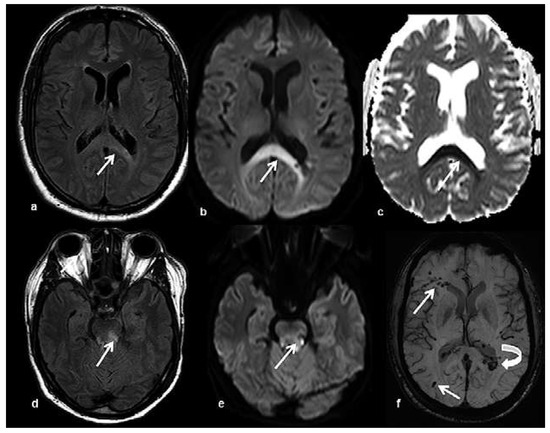

Head and brain trauma: general aspects and neuroimaging

by Johanna Maria Lieb, Christoph Stippich and Meritxell Garcia

In this article the general clinical aspects, imaging indications and different injury mechanisms of traumatic brain injury (TBI) are reviewed. In addition, the different imaging modalities and strategies are presented, including more specific imaging features of the various injuries. Computed tomography (CT) is [...] Read more.

In this article the general clinical aspects, imaging indications and different injury mechanisms of traumatic brain injury (TBI) are reviewed. In addition, the different imaging modalities and strategies are presented, including more specific imaging features of the various injuries. Computed tomography (CT) is the imaging modality of choice in the acute phase owing to its wide availability and short scanning time, as well as to its high sensitivity for the detection of fractures and acute bleeding. Although magnetic resonance imaging (MRI) is superior to CT in many other aspects, it plays no role in the acute phase. MRI, however, has been proven to be useful and complementary to CT in the subacute and chronic stages as well as in the case of inconclusive results on initial CT. Especially the use of standard sequences like fluid attenuated inversion recovery (FLAIR), diffusion and susceptibility weighted imaging (DWI and SWI) have been shown to increase the diagnostic potency in diffuse axonal injury, in mild brain trauma and also in more chronic stages of TBI. The use of more advanced MRI techniques such as diffusion tensor imaging (DTI), magnetic resonance spectroscopy (MRS), functional MRI (fMRI) and magnetic transfer imaging (MTI) can further complete the diagnostic evaluation and give insights into different pathophysiological processes in TBI. Full article